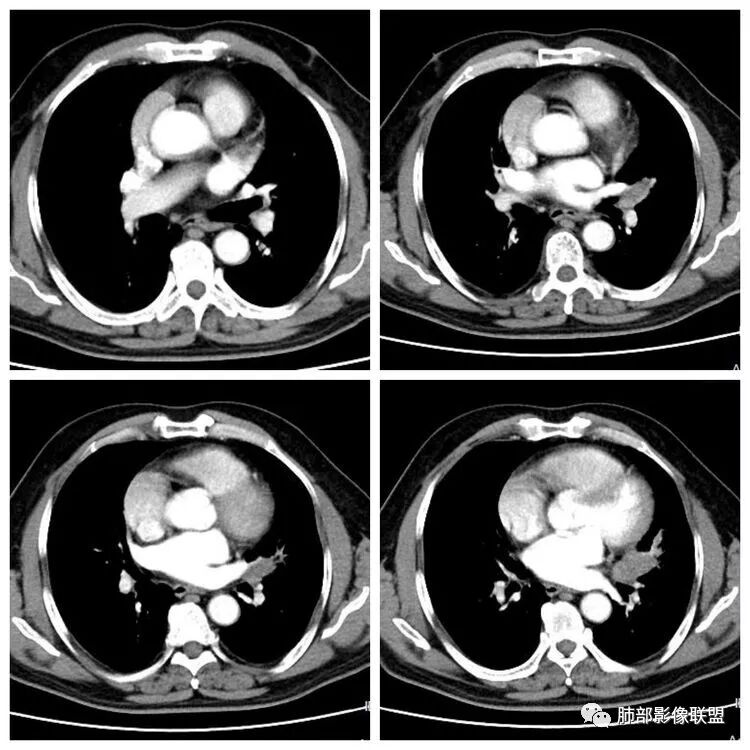

患者,男 ,66岁, “左肺占位”收住院。CEA   5.23 轻度增高

平扫 动脉期 静脉期  40HU、48HU、57HU

左上肺光滑圆形结节,内有钙化,密度不均,错构瘤;

左肺下叶结节支气管进入截断,远端肺不张,增强后坏死不均匀,肺癌明显,至于病理类型,鳞癌,小细胞,腺癌都有支持和不支持的地方,个人倾向于鳞癌可能,理由,纵隔淋巴结肿大不明显,远端阻塞性不张,支持小细胞的地方,坏死呈沼泽样,但纵隔无明显淋巴结肿大及冰冻表现。腺癌这种表现一般为低分化腺癌,但远端阻塞性不张及纵隔无明显淋巴结肿大不支持。

3.左肺上叶另见孤立结节影,边界清楚光整,中央钙化,未见脂质密度特征。

左肺上叶孤立小结节影未见异常强化。

5.双肺门及纵隔未见明确增大淋巴结。

7.左肺上叶孤立小结节影中央钙化可见于肠道肿瘤,但更多见于错构瘤,或是结核球。